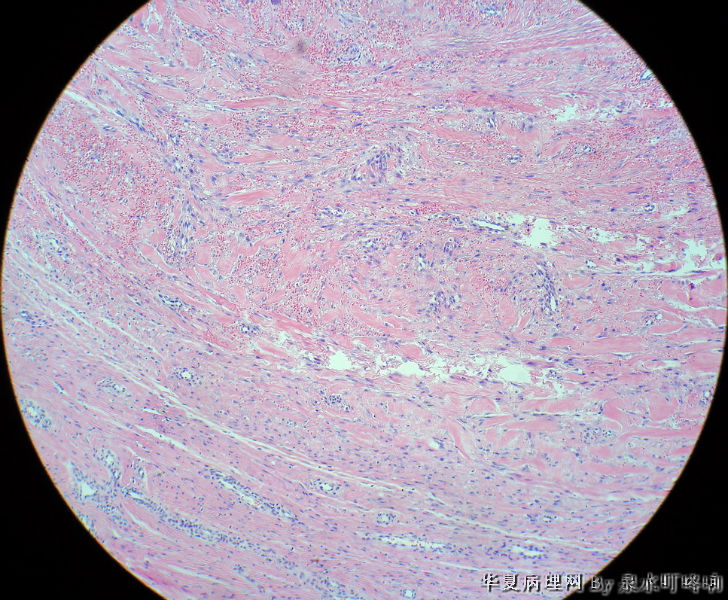

男,49岁,左肩胛部肿物。

图1